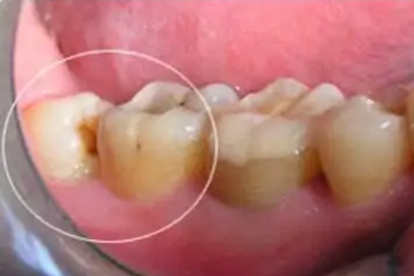

智齿存在阻生、倾斜生长或部分萌出时,通常需要拔除。阻生智齿可能压迫邻牙根,导致牙列拥挤或邻牙松动。部分萌出的智齿周围易形成盲袋,食物残渣堆积可能引发冠周炎,表现为红肿、疼痛甚至张口受限。反复发作的炎症可能扩散至颌面部间隙,形成脓肿。阻生智齿还可能增加邻牙龋坏或牙槽骨吸收的风险,此时拔牙是预防并发症的有效手段。